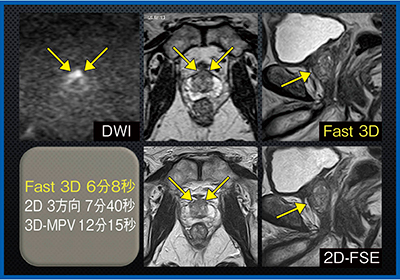

また,近年行われるようになった前立腺がんのロボット手術の新たな術式である後方アプローチにおいて,がんの詳細な位置関係の把握にFast 3Dが有用性を発揮すると思われる。症例5は前立腺がん症例であるが,Fast 3Dでは尖部の病変が境界明瞭で,被膜の構造もしっかりと描出されている(図5)。撮像時間も2D 3方向の撮像に比べて約1分短縮している。

図5 症例5:前立腺がん(70歳代,男性)